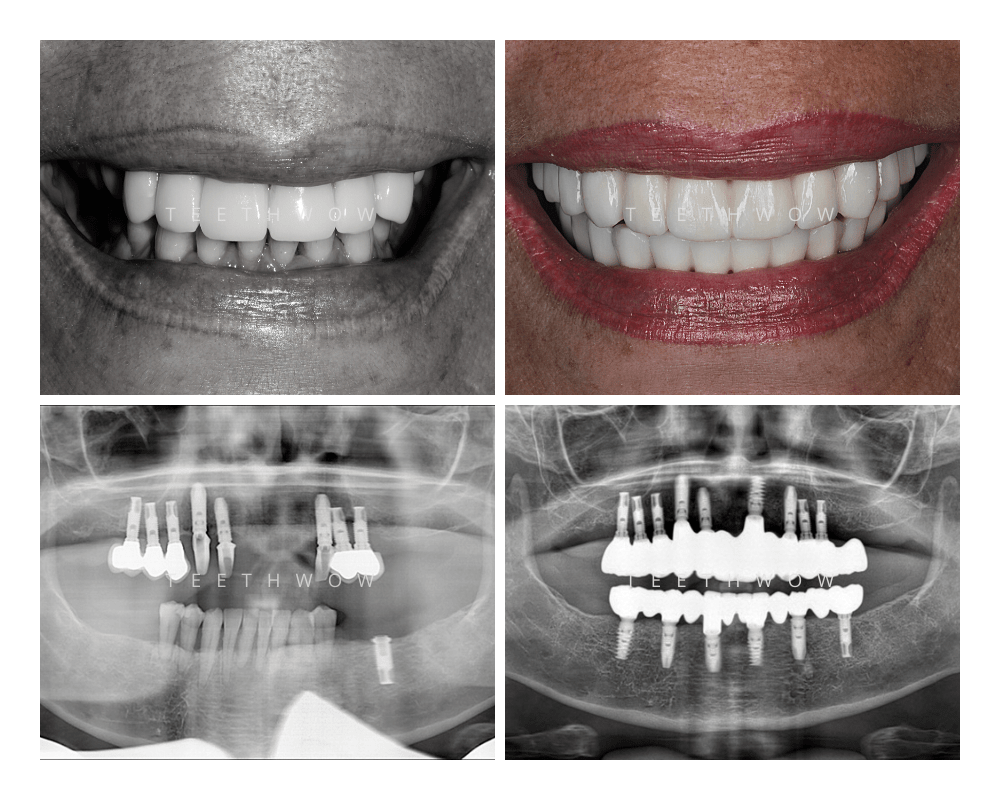

OUR RESULTS

Before and After Cases